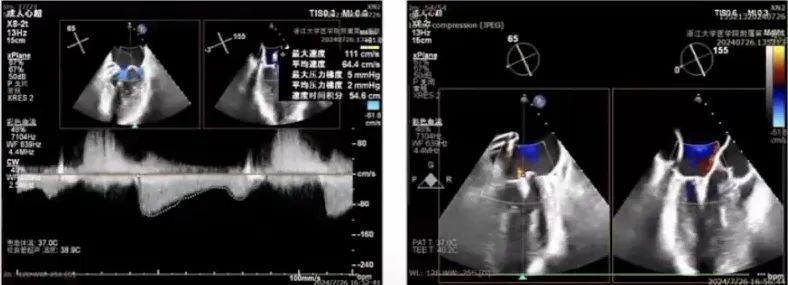

患者女性,76岁,主诉活动后出现胸闷气促1月。既往有原发性高血压病史。诊断为退行性二尖瓣反流(DMR),Carpentier分型为Ⅰ型,基础二尖瓣反流程度达5+,属极重度反流。超声心动图评估显示左心房明显扩大,左心室舒张末期内径(LVEDD)为6.0cm,左心室射血分数(LVEF)为72%。肺动脉收缩压(PASP)升高至58mmHg,提示合并肺动脉高压,三尖瓣反流为轻至中度。

经胸超声评估

经胸超声评估显示,二尖瓣前叶脱垂,并可见广泛反流。

经食道超声检查

经食道检查结果显示,1区瓣叶结构良好,主要脱垂集中于P2区,3区未见明显受累。

进一步评估患者病变情况,前叶长度2.74mm,后叶长度1.93mm;房间隔前后径4.0cm,房间隔长径6.9cm,瓣口面积6.27cm²,平均跨瓣压差5mmHg。

术前可见肺静脉逆流,术后则消失,反流明显改善。跨瓣压差由术前的19mmHg降至术后8mmHg,瓣膜血流动力学明显优化。同时,LVEDD由术前的6cm逐渐降至<5.0cm,患者左心室容量负荷减轻,心腔重构趋势明确,手术取得良好近期疗效。

术前

术后

术前

术后